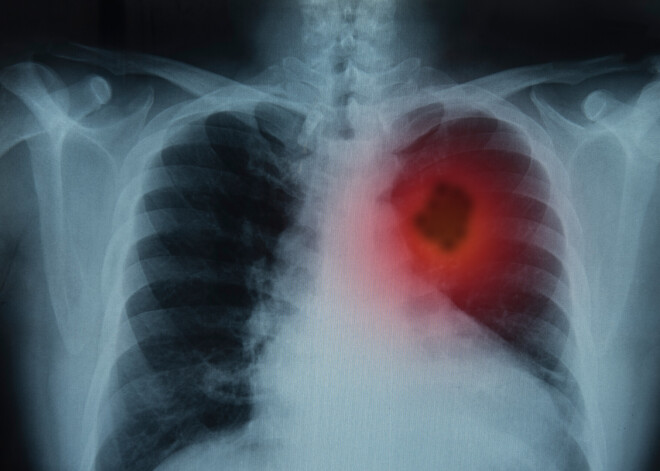

Pasaulē ir trīs vēža veidi, kas 2020. gadā nogalināja visvairāk cilvēku, tie bija plaušu vēzis (1,80 miljoni nāves gadījumu), kolorektālais vēzis (935 000 nāves gadījumu) un aknu vēzis (830 000 nāves gadījumu).

Kuri ir 10 nāvējošākie vēža veidi, saskaņā ar ASV Vēža institūta datiem?